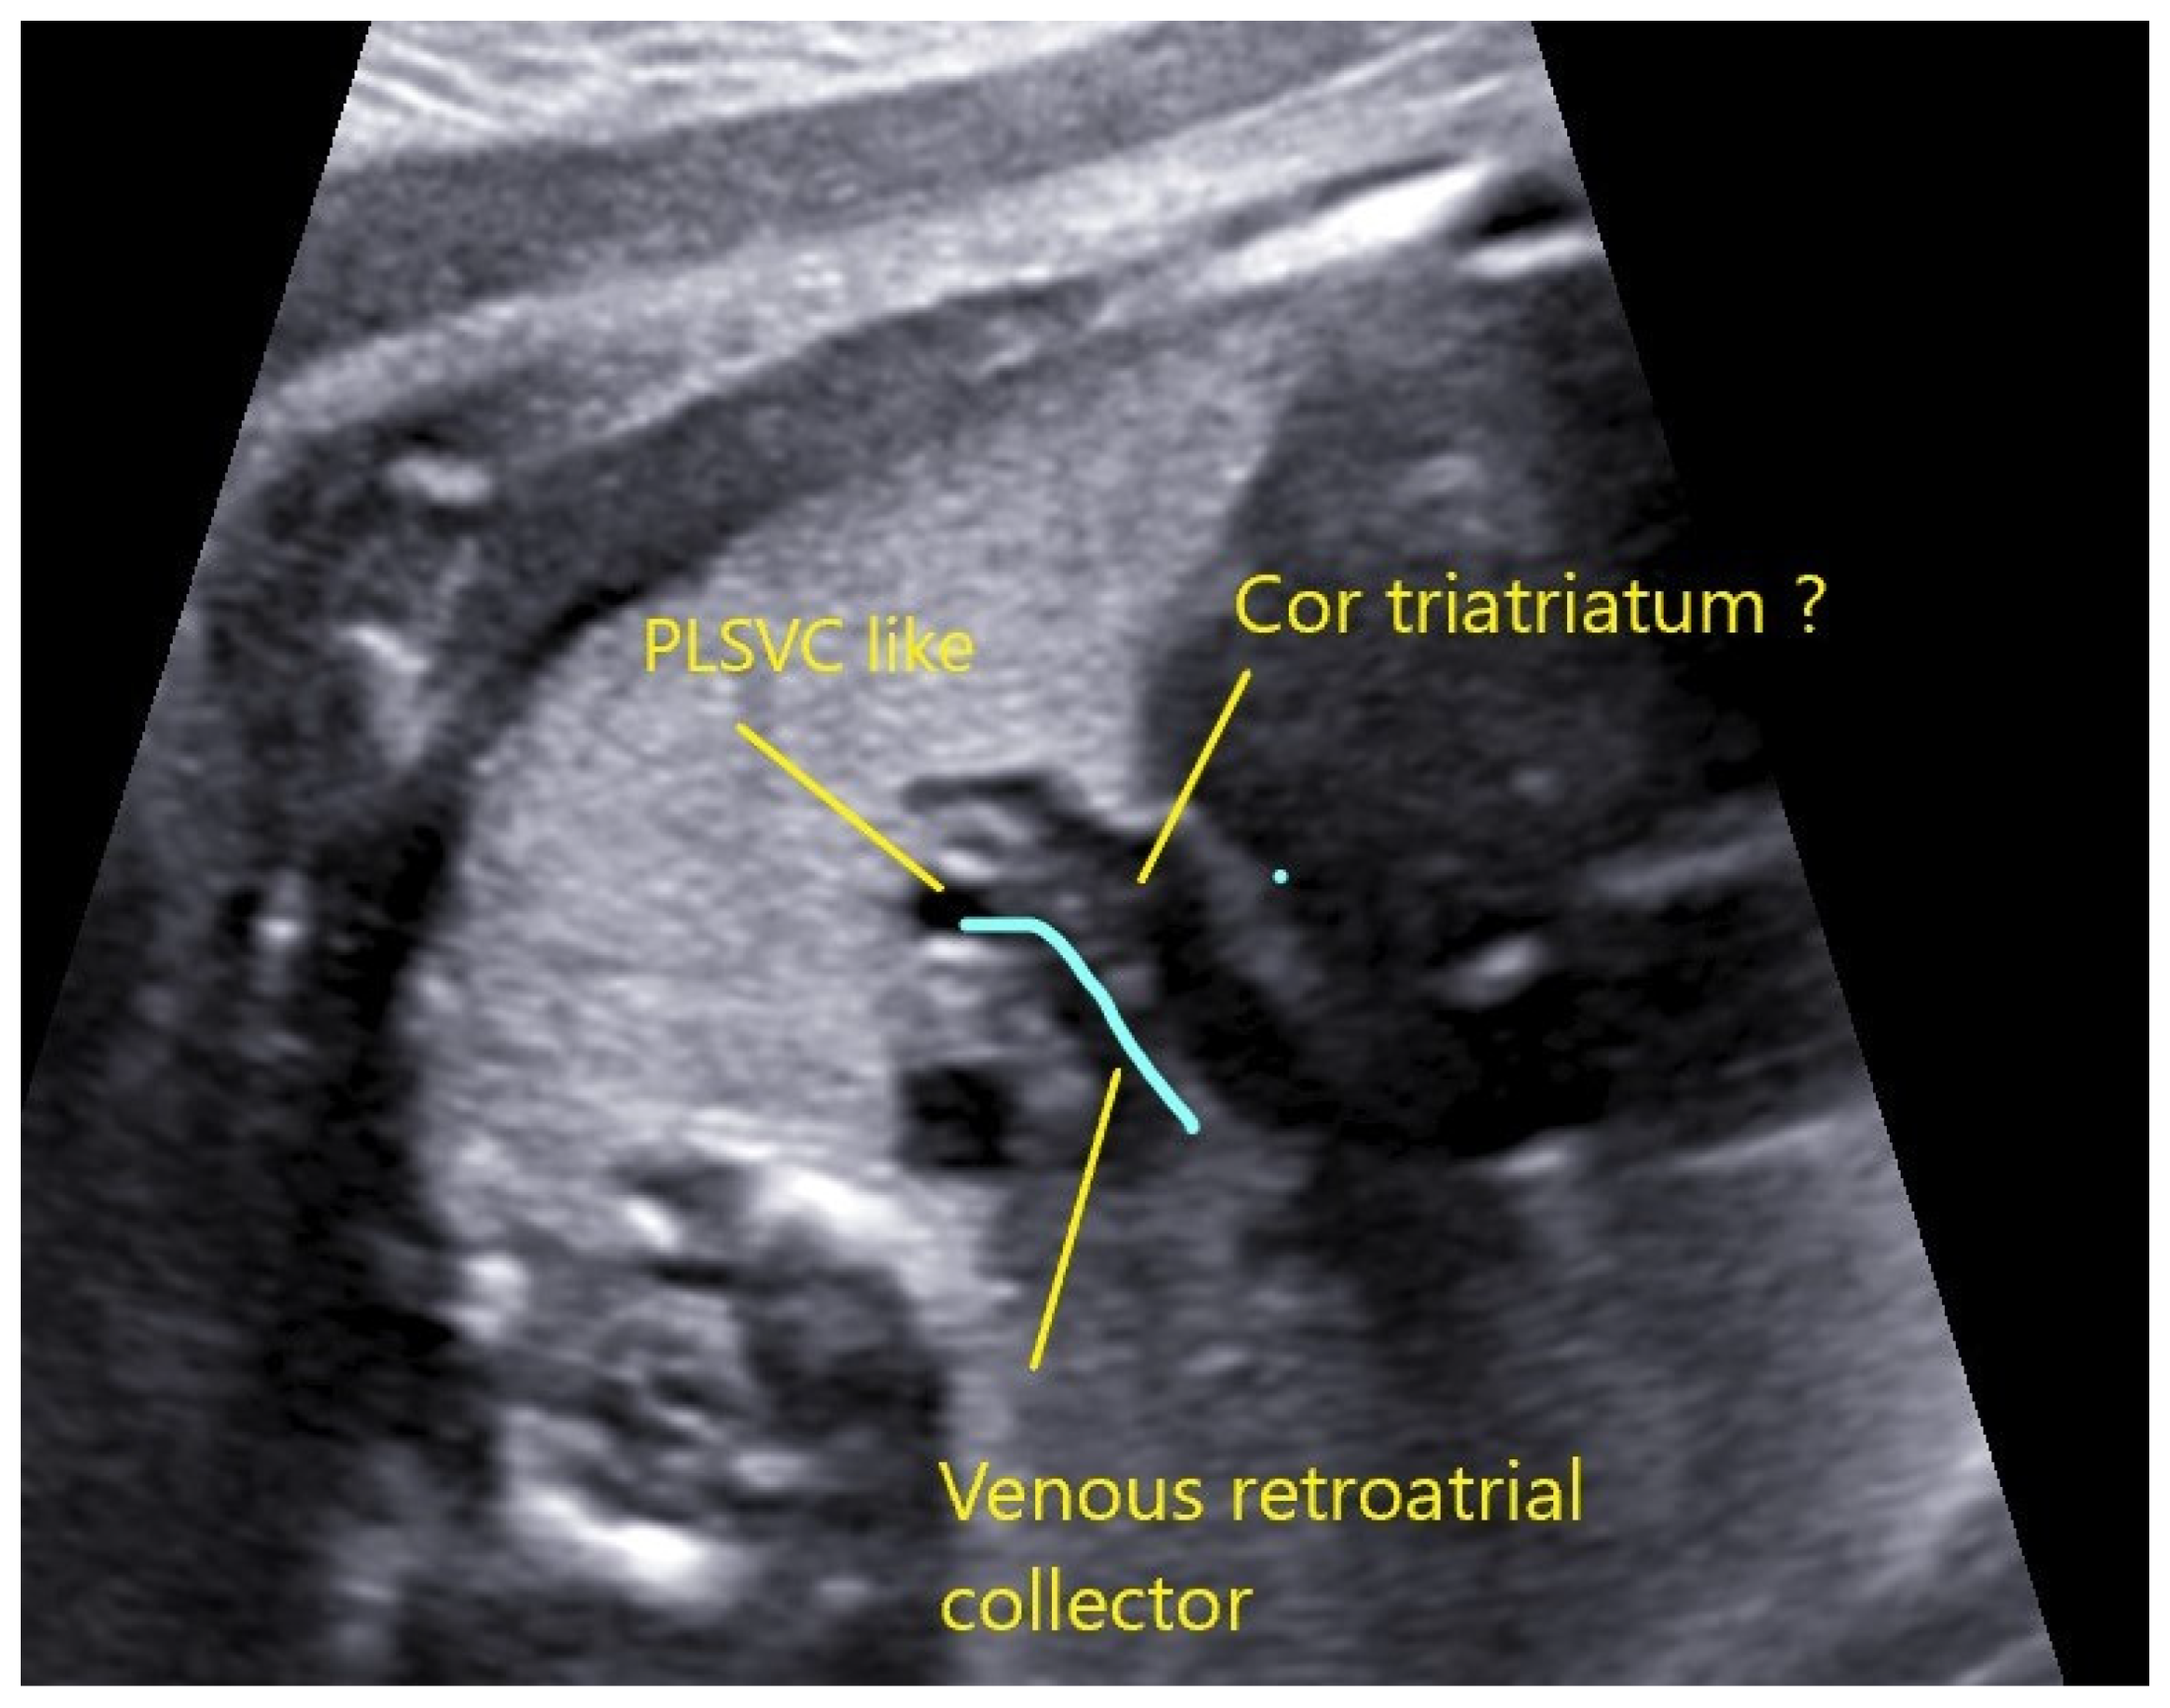

4.2. Case 2

4.3. Case 3

4.4. Case 4